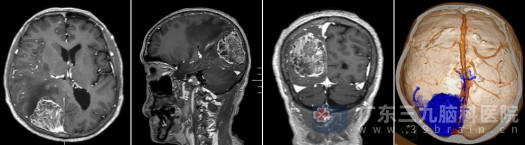

进一步的检查揭示了这场战役的艰巨性。术前MR显示,这个位于右侧顶枕部的巨大团块信号混杂,血供丰富,周围脑组织水肿严重。更关键的是,术前CTA发现,肿瘤不仅紧贴着大脑最重要的血液回流通道——上矢状窦,还将其部分包绕,区域内血管纵横交错。这意味着手术稍有不慎,就可能引发出血难止或静脉回流障碍,导致严重脑水肿甚至生命危险。

外十科团队术前高度警惕:患者年逾古稀,肿瘤位置深、关系复杂,手术无疑是在生命中枢的血管丛林中“排雷”。然而,面对患者和家属的信任与期盼,团队没有退缩。他们利用三维影像技术,反复推演每一步操作,制定了以“最大程度切除肿瘤、最大程度保护脑功能、尽全力保全血管”为核心的个体化手术方案。